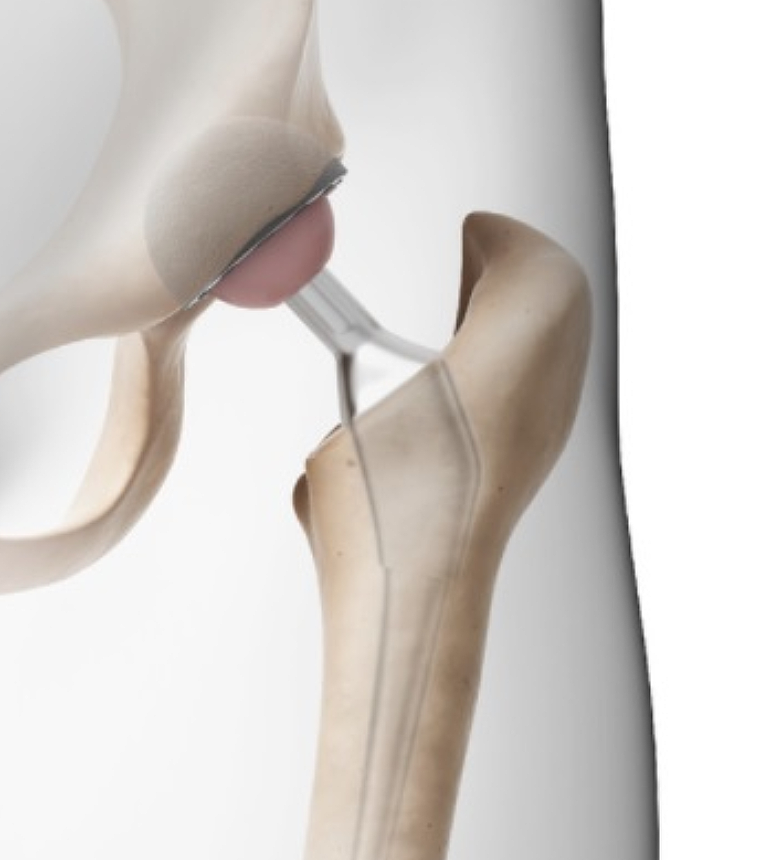

고관절은 골반 뼈 속에 공처럼 생긴 대퇴골의 골두가 맞물린 관절입니다. 대퇴골두는 다른 부위에 비해 혈액 순환 장애가 쉽게 올 수 있으며, 혈액 순환 장애는 대퇴골두 무혈성 괴사를 유발합니다. 뼈가 썩으면 몸의 하중을 정상적으로 견디지 못해 미세구조에 골절이 생기고, 심각한 통증이 발생합니다.